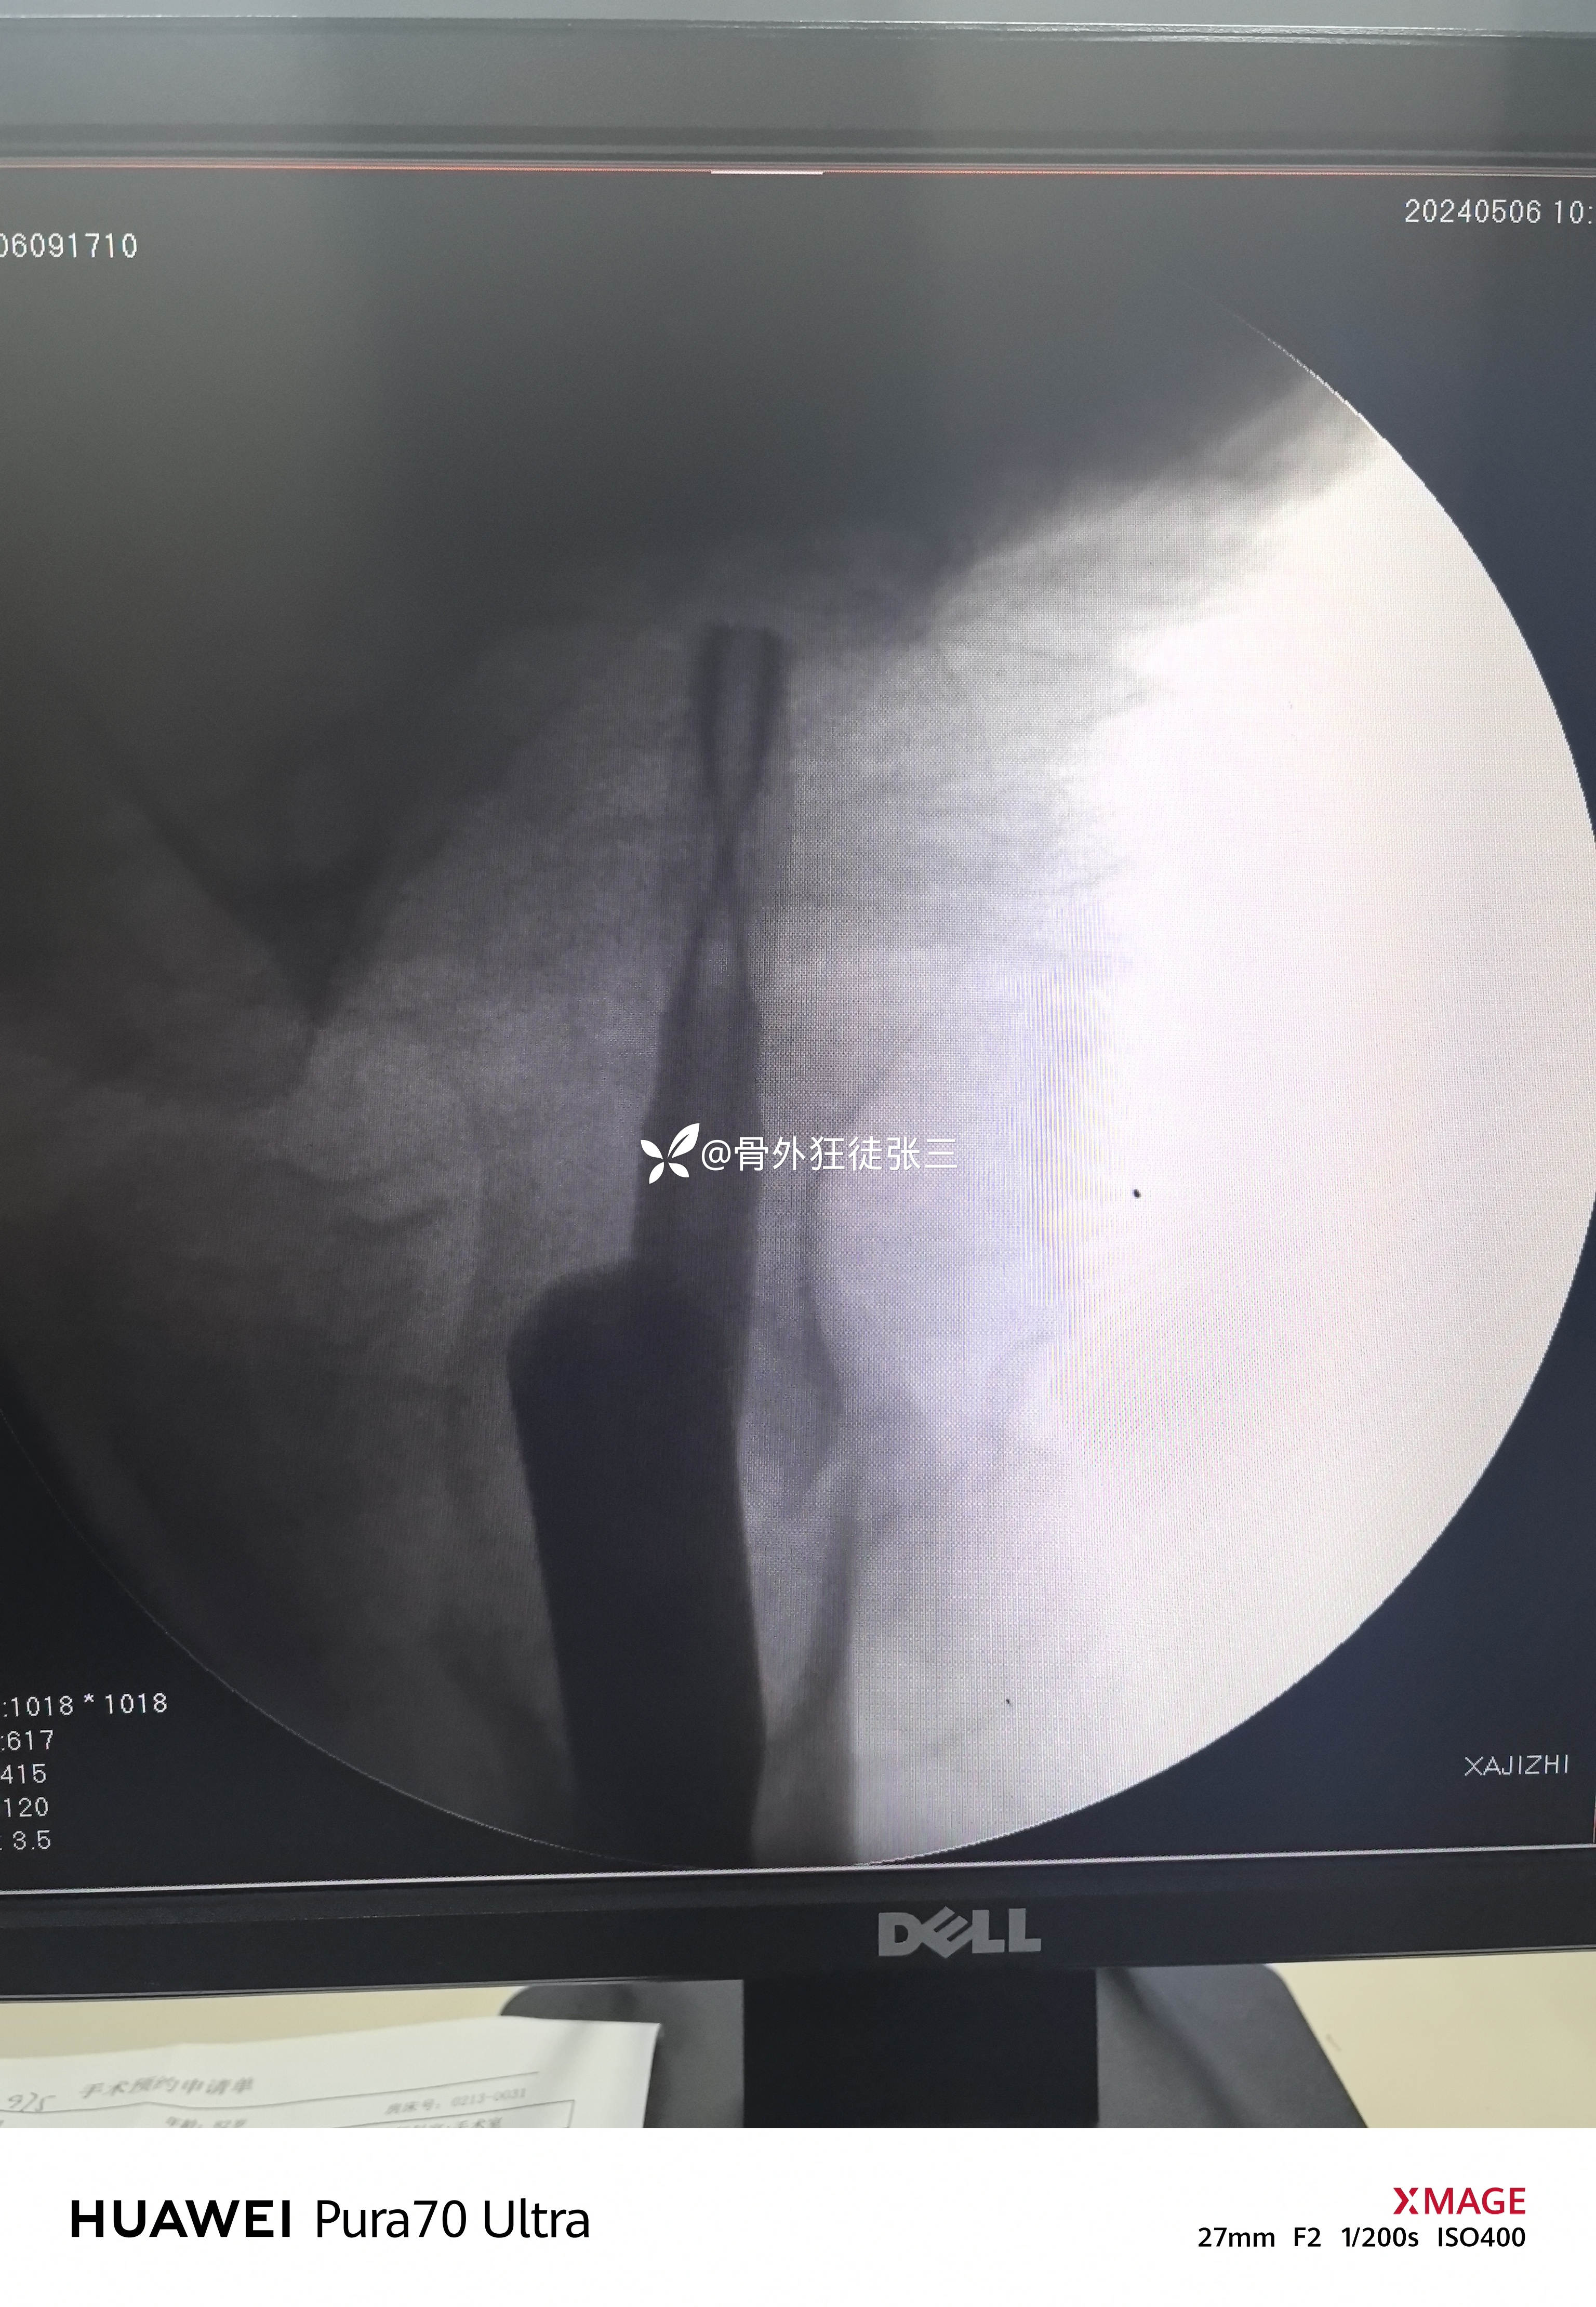

牵开器——透视正侧位——切口——确定进针点——铰刀开口——开口钻开口——金手指——导针置入——直接使用170 mmX12 mm主钉插入——调整前倾主钉深度和前倾——透视正位中下1/3,侧位基本居中——远端锁钉——近端锁尾端尾帽,——再次透视正、侧、蛙位——冲洗、缝合1-1-3 ——09:37-10:16 ——40分钟手术结束,透视16次,每次约一分钟,手术操作20分钟。

没有再调整主钉和螺旋刀片

螺旋刀片还能再长5mm